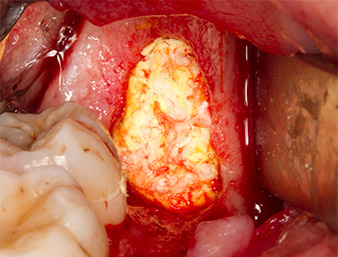

Um autogenes Material für die spätere Wundversorgung zu gewinnen, wurden mit einem piezochirugischen Instrument (Piezomed B5) gesunde Knochenspäne aus der Umgebung des Wurzelrests gewonnen (Abb. 5).

Piezomed B5

Abb. 5: Mit einem meißelförmigen piezochirurgischen Instrument (Piezomed B5) wird Knochen im Bereich der Alveole abgehoben. Dieser dient nach Entfernung des Wurzelrests als autologes Augmentationsmaterial

(vgl. Abb. 13 und 14).

Das autogene Gewebe wurde mit dem schaufelförmigen Arbeitsteil des Instruments entnommen und bis zur weiteren Verwendung in physiologischer Kochsalzlösung aufbewahrt (vgl. Abb. 13).